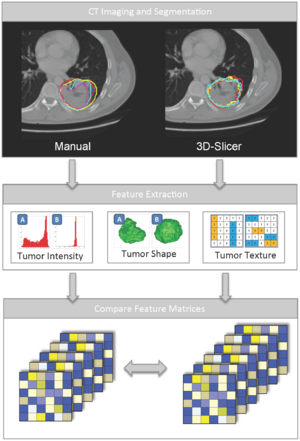

- 4.21 Robust Radiomics Feature Quantification using Semiautomatic Volumetric Segmentation

- 4.46 Robust Radiomics Feature Quantification using Semiautomatic Volumetric Segmentation